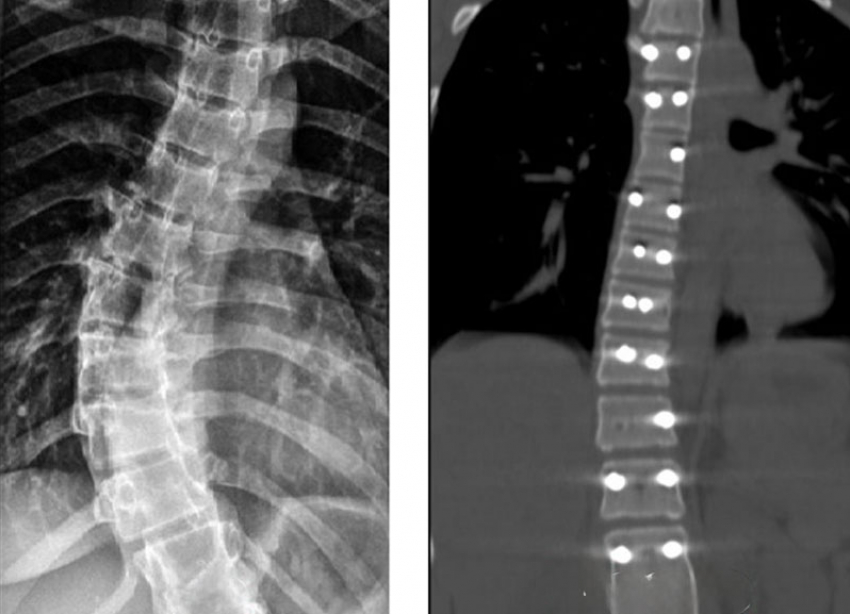

В Ставропольской краевой клинической больнице успешно выполнили очередную сложную операцию по коррекции сколиоза у 14-летней пациентки. Хирургам удалось исправить деформацию и остановить прогрессирование болезни. Об этом сообщили в пресс-службе Ставропольской краевой клинической больницы.

На этот раз помощь потребовалась 14-летней девушке с идиопатическим сколиозом. У нее был выявлен изгиб позвоночника в 40 градусов. Такой уровень деформации со временем может повлиять на работу сердца и легких. Врачи приняли решение о хирургическом лечении, чтобы остановить развитие заболевания и вернуть позвоночнику правильное положение.

Во время операции пациентке установили надежную металлоконструкцию, фиксирующую позвоночник в выпрямленном состоянии. После операции девушка быстро пошла на поправку и уже выписана домой.